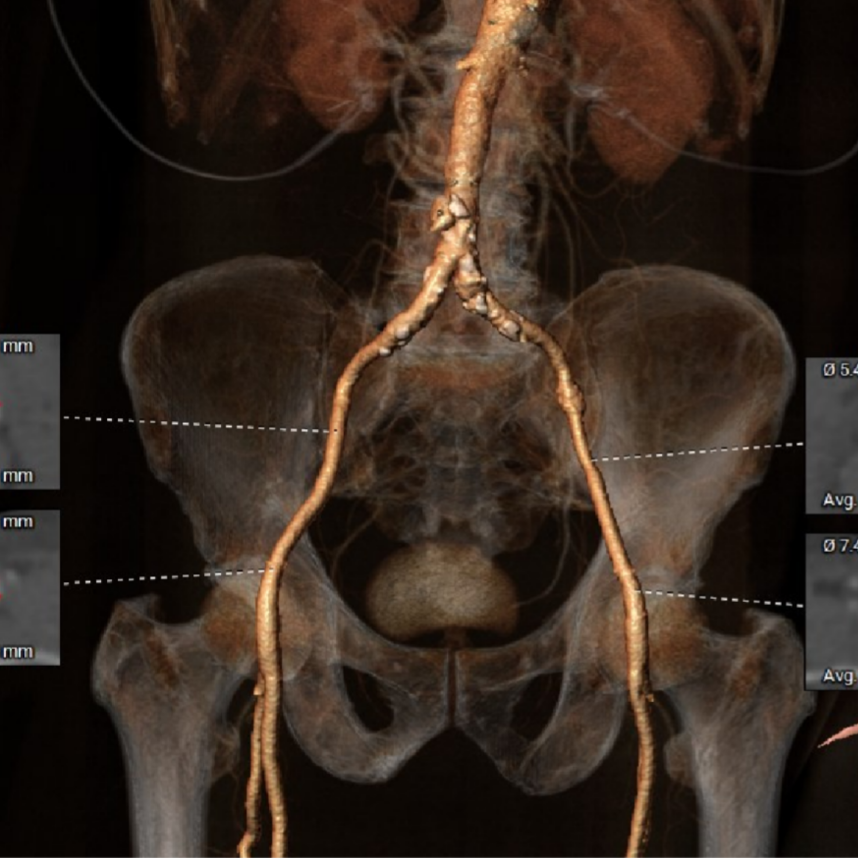

辅助检查:主动脉CTA可见腹主动脉夹层。

术前CT评估-TAVI viv

Annulus——内径

Annulus——外径

瓣架高度

LVOT

瓣上2mm

瓣上4mm

瓣上10mm

瓣上14.6mm

Sinotubular Junction

Ascending Aorta

SOV Diameter

Hockey Puck (VR)

LCA Height

RCA Height

LV&LA

LV

右窦中心

释放角度

肋间选择

钙化

血管入路

冠脉风险:LCA:8.0mm,RCA:11.4mm;外科瓣术后,SOV:34.0*36.3*36.4mm,STJ:33.8mm,冠脉堵塞风险低;